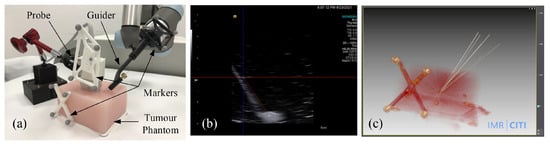

We further conducted biopsy experiments on a soft tumor phantom (LYDMED, China) to validate the potential of the proposed system for tumor biopsy. The soft tumor phantom is made of silicon rubber and has a size of 150 × 120 × 80 mm 3 , as shown in Figure 11.

There is a simulated tumor with a diameter of about 10 mm embedded inside the soft phantom. In addition, an optical reference frame was fixed to the phantom. The planned trajectories in the COS of the reference frame were obtained by using the method introduced in [28], which was treated as the ground truth. A needle with a diameter of 0.8 mm was inserted into the phantom via the passage of guide, and it was kept inside the phantom. We repeated the same procedure six times, and every time we planned different target points and aiming trajectories. After needle insertion, we obtained a CT scan of the phantom. The biopsy accuracy were then measured in the 3D CT imaging space.

The overall system performance was evaluated by needle biopsy on a tumor phantom. Results of the tumor phantom experiment are presented in Table 5. The success rate of the needle biopsy into the tumor was 100 % . An average distance error of 1.71 mm and an average angular error of 1 . 0 were found. We attributed the relatively large errors to the elastic deformation of the biopsy needle during insertion. Nonetheless, the achieved accuracy is good enough for the target applications and is better than the results achieved by most of the state-of-the-art methods [2,3,8,13,29].

Figure 11. Soft tumor phantom biopsy experiments. (a) experimental setup including a robot arm with the guide, the soft tumor phantom with a reference frame atached, and the biopsy needle; (b) US image of a biopsy needle inserting into the tumor phantom; (c) CT image of the phantom after needle insertions.